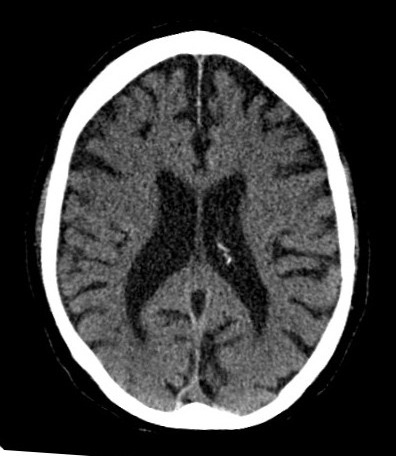

- Computed Topography – can be used for an intensive and more detailed imaging of injuries and abnormalities in the anatomical pathology (e.g. detection of pulmonary emboli or airway tumor).